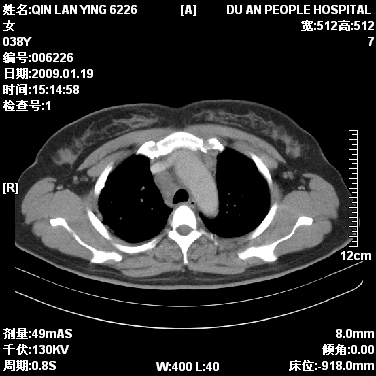

标题: CT17781:女,38岁,胸疼1个月。

女,38岁,胸疼1个月。wbc:1万4

1)右肺中央型肺癌并右肺上叶阻塞性肺炎、节段性肺不张,纵隔淋巴结转移、右侧胸膜转移、肝脏转移。2)右侧胸腔少量积液。

1、右侧中央型肺癌并阻塞性肺不张,纵隔内、主动脉弓旁、右肺门淋巴结及肝脏转移可能性大,建议纤支镜进一步检查。

2、右侧胸腔积液。

本病例有几个容易诊断的地方:1、右肺上叶前段支气管闭塞,肺不张。2、淋巴结明显肿大。3、肝脏多个类圆形低密度影呈“牛眼征”改变,高度提示转移。

从影像学角度分析      右肺上叶中央型肺癌,并阻塞性不张、肺炎,纵隔淋巴结、膈顶淋巴结转移。